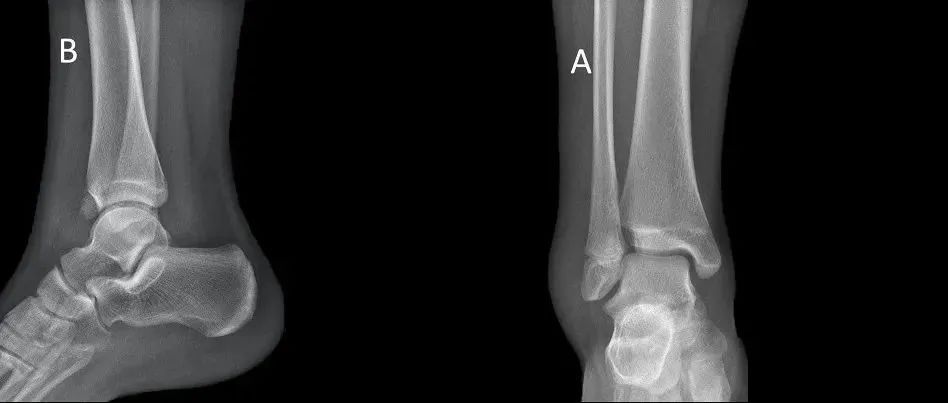

Tillaux 骨折:小骨折大陷阱!

Tillaux 骨折是累及胫骨远端骨骺的关节内骨折,约占所有胫骨远端骨骺损伤的 2.9%。单靠 X 片容易漏诊,一旦误诊或漏诊导致踝关节不匹配、不稳定,患者会遗留疼痛甚至发展为创伤性关节炎。Tillaux 骨折。箭头所指为下胫腓前韧带。图源:DOI: 10.1302/2058-5241.6.200042.损伤机制Tillaux 骨折常为旋后外旋损伤所致,是下胫腓前韧带附着骨块的骨折,骨折线涉及冠状面、矢状面、横断面。Tillaux 骨折常发生于胫骨远端骨骺闭合前的 18 个月,此时正处于过渡阶段(胫骨远端骨骺部分闭合,部分未闭合)。...